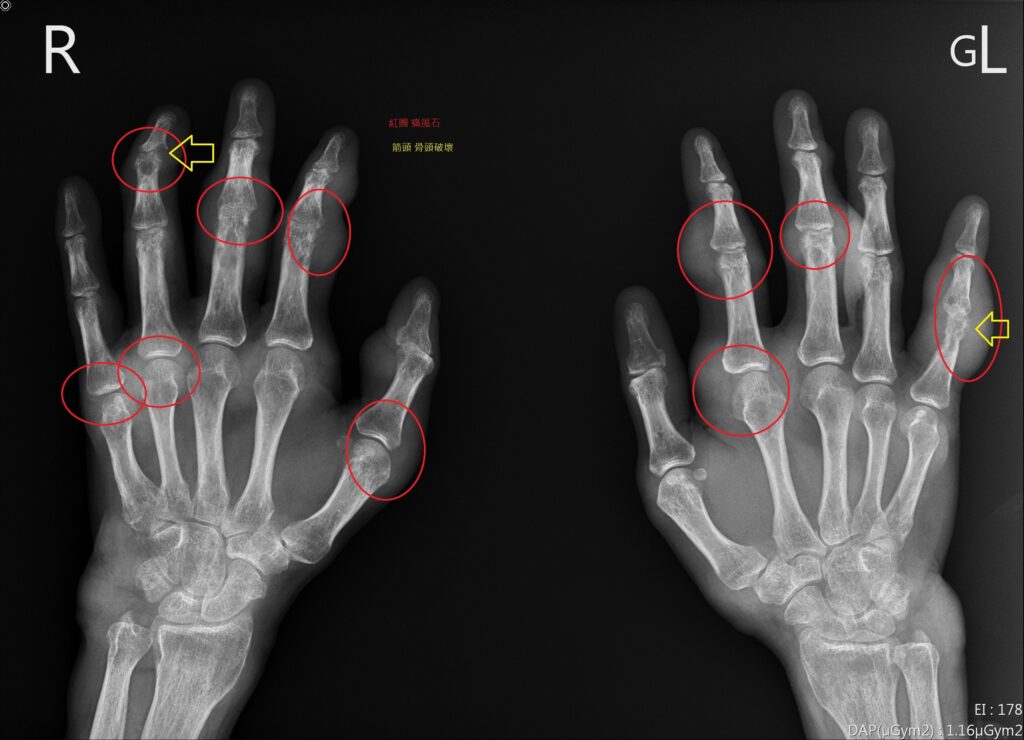

<figure class="wp-block-image size-large"><img loading="lazy" decoding="async" width="1024" height="740" src="https://wellnews.media/wp-content/uploads/2023/03/gout-2-1024x740.jpg" alt="" class="wp-image-6760" srcset="https://wellnews.media/wp-content/uploads/2023/03/gout-2-1024x740.jpg 1024w, https://wellnews.media/wp-content/uploads/2023/03/gout-2-300x217.jpg 300w, https://wellnews.media/wp-content/uploads/2023/03/gout-2-768x555.jpg 768w, https://wellnews.media/wp-content/uploads/2023/03/gout-2-1536x1110.jpg 1536w, https://wellnews.media/wp-content/uploads/2023/03/gout-2-2048x1480.jpg 2048w, https://wellnews.media/wp-content/uploads/2023/03/gout-2-324x235.jpg 324w, https://wellnews.media/wp-content/uploads/2023/03/gout-2-696x503.jpg 696w, https://wellnews.media/wp-content/uploads/2023/03/gout-2-1068x772.jpg 1068w, https://wellnews.media/wp-content/uploads/2023/03/gout-2-581x420.jpg 581w, https://wellnews.media/wp-content/uploads/2023/03/gout-2-1920x1387.jpg 1920w" sizes="(max-width: 1024px) 100vw, 1024px" /><figcaption class="wp-element-caption"><strong>痛風患者手部X光片，紅圈為痛風石，黃色箭頭為遭破壞骨頭。(圖/花蓮慈濟醫院堤供)</strong></figcaption></figure>